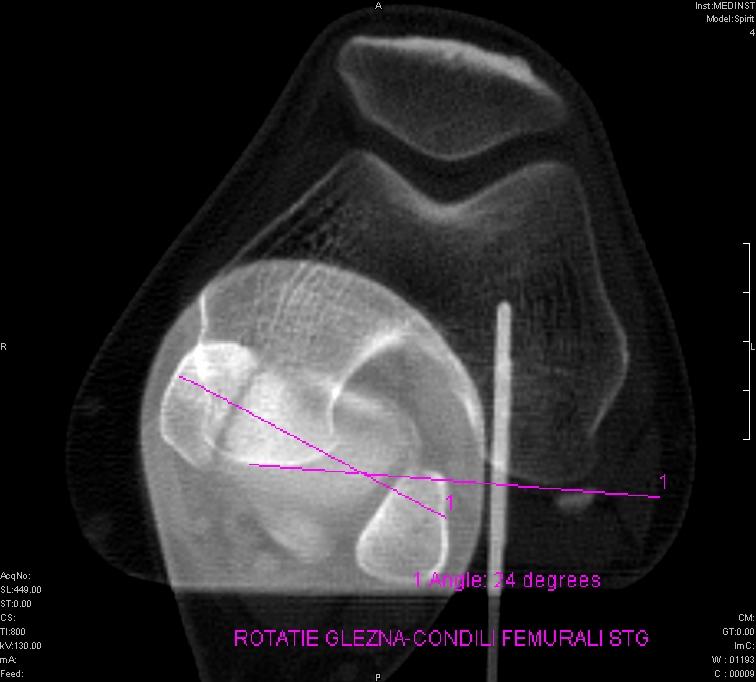

- măsuratori de stabilitate rotuliană;